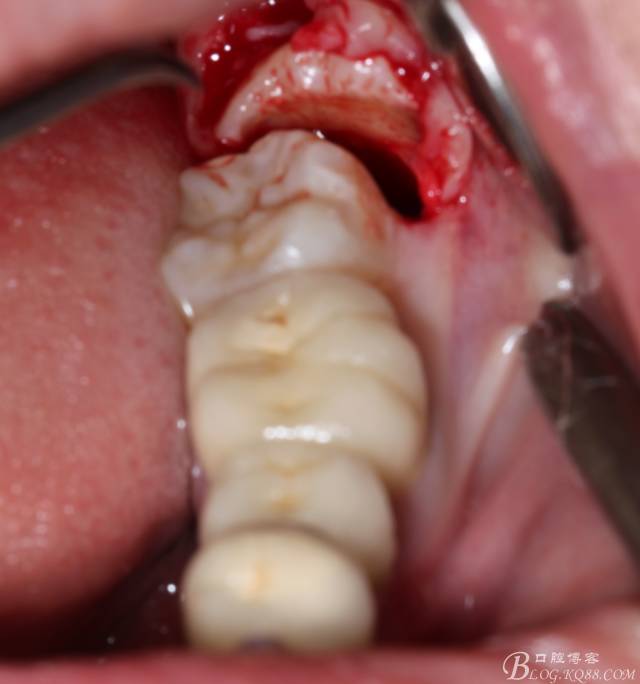

取出阻力部分冠

在取出阻力冠后,嘗試性看能取出全部的牙體不,就是取不出也能整體撬動(dòng)牙根。